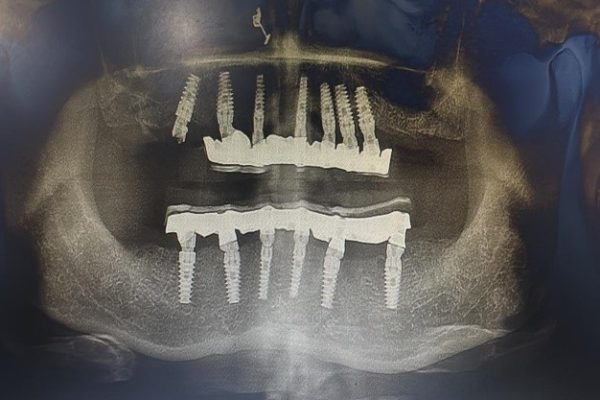

Before-After